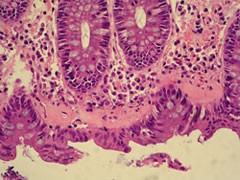

Kollagene Kolitis HE (stärkere Vergrößerung)